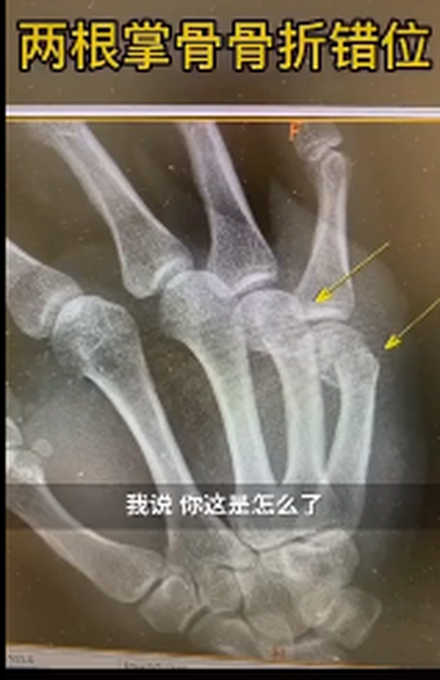

近日,上海新华医院骨科接诊了一男性患者。该患者右手第四第五掌骨肿胀明显。新华医院骨科主治医师王晖询问后得知,原来这名患者是在家辅导孩子作业时,因孩子作业做得不理想,生气但舍不得打孩子,自己捶墙,没想到把自己捶骨折了。